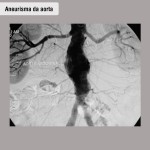

Aneurisma da aorta abdominal

O que é

Fraqueza da principal artéria do abdômen causada pelo depósito de colesterol e cálcio na parede da artéria, fazendo-a dilatar como um balão. Trata-se de um processo lento e gradual, que pode levar anos. Acontece com mais frequência em pacientes com problemas vasculares, doenças do coração, pressão arterial elevada e fumantes.

A tomografia computadorizada de abdômen é o principal exame para revelar e avaliar o tamanho do aneurisma. Também é comum recorrer à angiografia para planejar o tratamento.